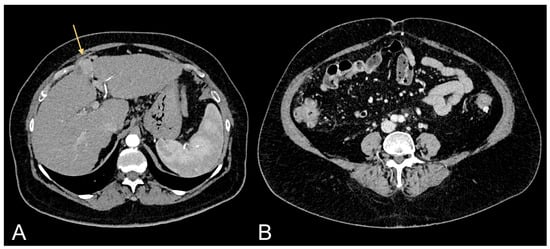

Figure 3.

Contrast-enhanced CT images of a 63-year-old male patient with excessive amount of VAT showing ccRCC (light orange arrow in (A)) and follow-up after tumorectomy (light orange arrow in (B)).